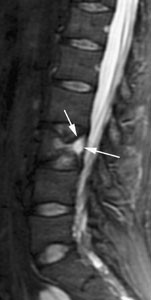

Fig. 2.